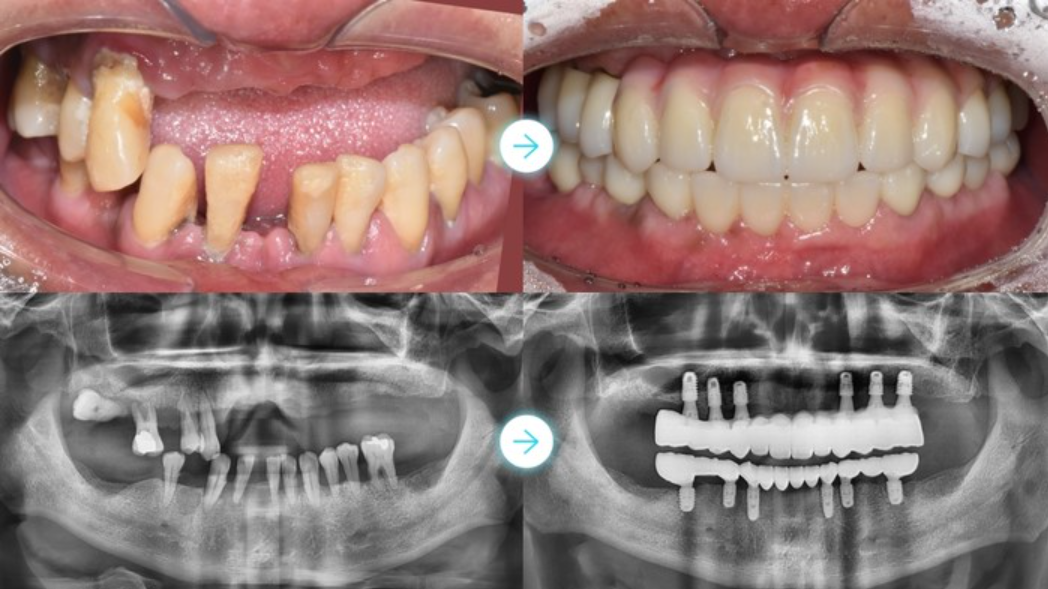

임플란트는 상실된 치아 자리에 인공 치근을 심어 자연치아의 기능을 회복시키는 치료법으로 알려져 있습니다. 서울대학교병원 자료에 따르면 임플란트는 크게 픽스처(인공 치근), 지대주(기둥), 크라운(인공 치관) 세 부분으로 구성되어 있으며, 각 부품의 재료와 브랜드에 따라 최종 비용이 달라진다고 합니다.

임플란트 수술 과정 단계별 설명

견적을 받을 때 독자분들이 가장 놀라시는 부분이 바로 비급여 부가수술입니다. 잇몸뼈가 부족하거나 치아 상실 기간이 오래돼 뼈가 흡수된 경우 아래 시술이 추가로 필요할 수 있고, 모두 건강보험이 적용되지 않는 항목이라고 알려져 있습니다.